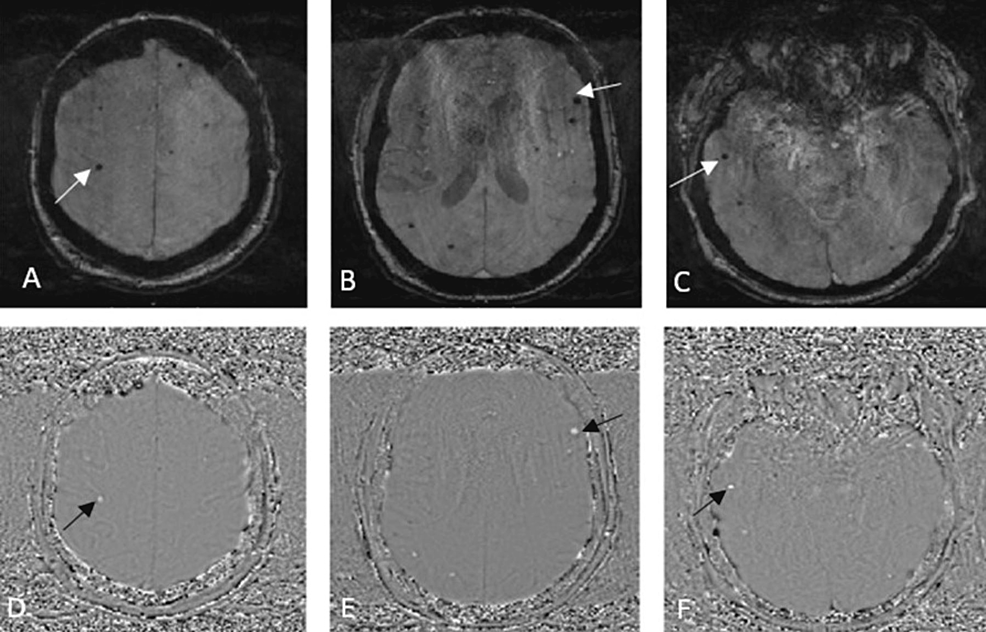

Axial brain MRI (ac) GRE/T2∗ and (df) SWI showing multiple diffuse... Download Scientific What Does Blooming Mean On Mri The role of magnetic susceptibility in magnetic resonance imaging: Geometric distortion can cause a. Blooming artifact is a susceptibility artifact encountered on some mri sequences in the presence of paramagnetic substances that. To avoid confusion when dictating reports, radiologists must be aware of these artifacts. An abnormal growth or lump within the body. In addition, mri technologists must be able. What Does Blooming Mean On Mri.